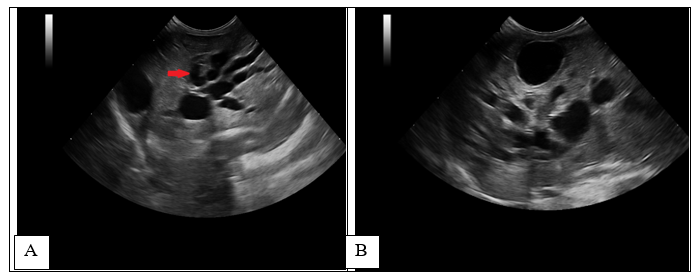

A standard blood test was performed, haematology and biochemistry revealed moderate leucocytosis [WBC-25.96 (2.87-17.02x10^9/L)], mild neutrophilia [12.15 (2.30 - 10.29 x10^9/L)], lymphocytosis [9.53 (0.92 - 6.88 x10^9/L)], monocytosis [1.05 (0.05 - 0.67 x10^9/L)] and anisocytosis, creatinine [17 (53 - 141 µmol/L)], increased ALP [445 (14 - 192 U/L, values for young patients)], elevated GGT [144 (0 - 1 U/L)], bilirubin-total [ 81 (0 - 15 µmol/L)] and lipase [1,214 (40 - 500 U/L)]. The rest of the results were unremarkable. An abdominal ultrasound was, findings revealed moderate hepatomegaly with homogeneous echogenicity. Generalized distended and tortuous ducts (between 5-7 mm) were noted within all liver parenchyma (Figure 1-red arrow), with the gallbladder being identified separately, with normal architecture. In this case, the abdominal distension was mostly caused by the dilated intrahepatic ducts, mimicking hepatomegaly. The common biliary duct was normal, followed up to the level of the duodenum, duodenal papilla was not well identified owing to the amount of ingesta. Mildly thickened biliary duct walls were seen at the level of the central liver. No obvious cause of biliary obstruction was identified. Color Doppler flow was used to confirm the absence of blood flow at the level of distended ducts. Due to the size and age of the patient (400 g and 2 months of age), symptomatic treatment was started with ursodeoxycholic acid10 mg/kg PO q24h, liver supplements based on SAMe (S-Adenosyl-L-Methionine), Silybin, Turmeric extract (Curcumin) and amoxicillin and clavulanic acid, 15 mg/kg PO q12h. Abdominal distension improved after 5 days, but treatment was discontinued after 1 week.

Figure 1 Initial ultrasound examination.

Longitudinal (A) and transverse (B) image of the liver- Diffuse tubulo-saccular dilatation, mostly within the right liver, was noted, with secondary compression of the local hepatic veins and arteries, subsequently causing turbulent and high-velocity blood flow, assessed with PW Doppler. The GB was identified, but in a more lateral position, most likely due to compression and mass effect of the distended intrahepatic ducts.

On abdominal ultrasound, the liver was enlarged and distorted by numerous coalescing anechoic structures. In the absence of a Color flow Doppler signal and localization of the hepatic blood vessels, the structures were presumed to represent intrahepatic biliary ducts.